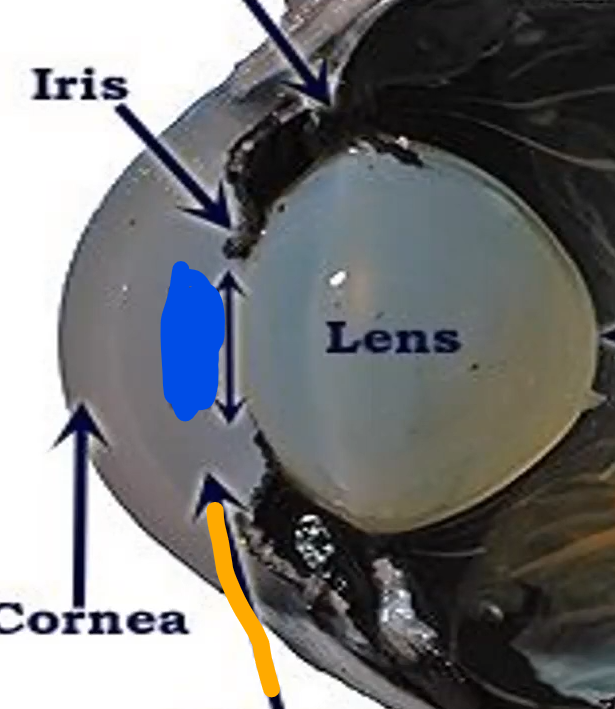

Orange

Iris

Blue

Pupil/lens

Red

Lens

Blue

Retina

Gray

Iris

Blue

Pupil